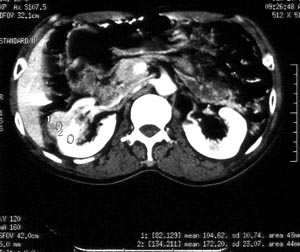

ct平扫加增强扫描:右肾中下极肾盂外侧段实质见分叶状软组织密度肿块,截面大约56x45mm,向外突破肾包膜,向内突入肾盂,平扫密度略不均,ct值32-37hu。c+见病灶不均匀轻-中度强化,内有未强化坏死区。右侧肾周筋膜增厚,右肾内前方见肿大淋巴结。

ct诊断:右肾癌,ct表现见上述,伴同侧腹膜后淋巴结转移。

手术所见:右肾大小15x7cm,背侧有肿物突出肾包膜,大小7x4cm。行“右肾癌根治术”。

手术病理:

透明细胞癌(ⅰ-ⅱ级)